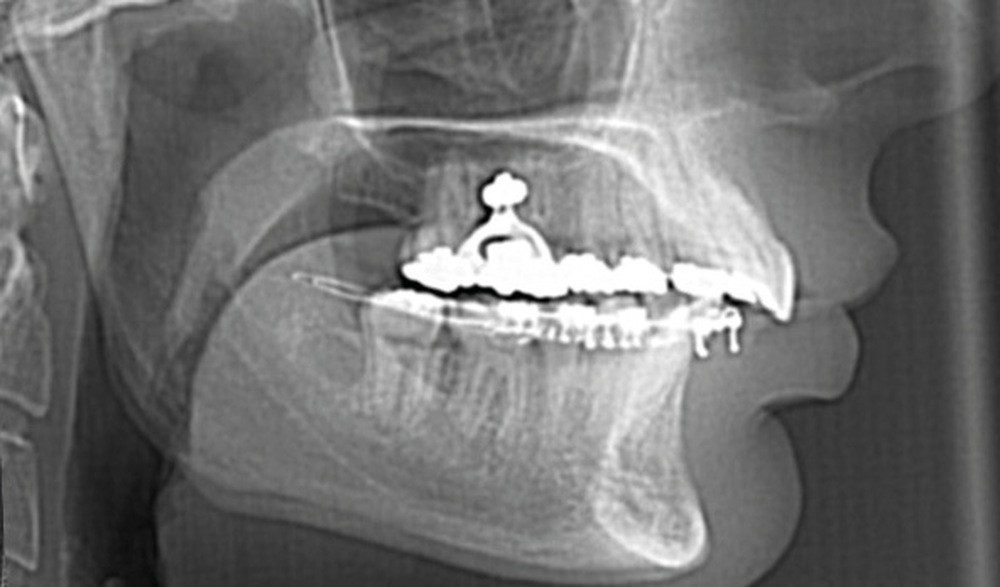

C’est à ces questions que nous permettront de répondre les deux premiers conférenciers, parodontologistes : le Dr Béatrice Straub nous présentera le renfort parodontal minéralisé, technique qu’elle a développée et pratique depuis de nombreuses années, pour éviter les préjudices des mouvements orthodontiques à risque, notamment lors des décompensations préchirurgicales (fig. 1a-d) ; le Pr Anton Sculean abordera le thème des greffes, avec leurs indications, les différentes techniques à privilégier et illustrera ses propos par de nombreux cas cliniques aux résultats esthétiques impressionnants.

À côté de la coopération moindre qu’ils exigent, les ancrages squelettiques présentent également l’avantage de répondre à des indications très variées : correction des sourires gingivaux (Dr Skander Ellouze, fig. 3a-c), distalisation ou mésialisation molaire, supports pour les masques faciaux, mini transpalatin sur vis après expansion, ressorts de rétraction pour mettre en place les canines incluses sans léser les racines des dents adjacentes [3] (Dr Stéphane Renger, fig. 4) ou appareils d’expansion maxillaire (Dr Hans Winsauer, Dr Guido Sampersmans, fig. 5a-c)…